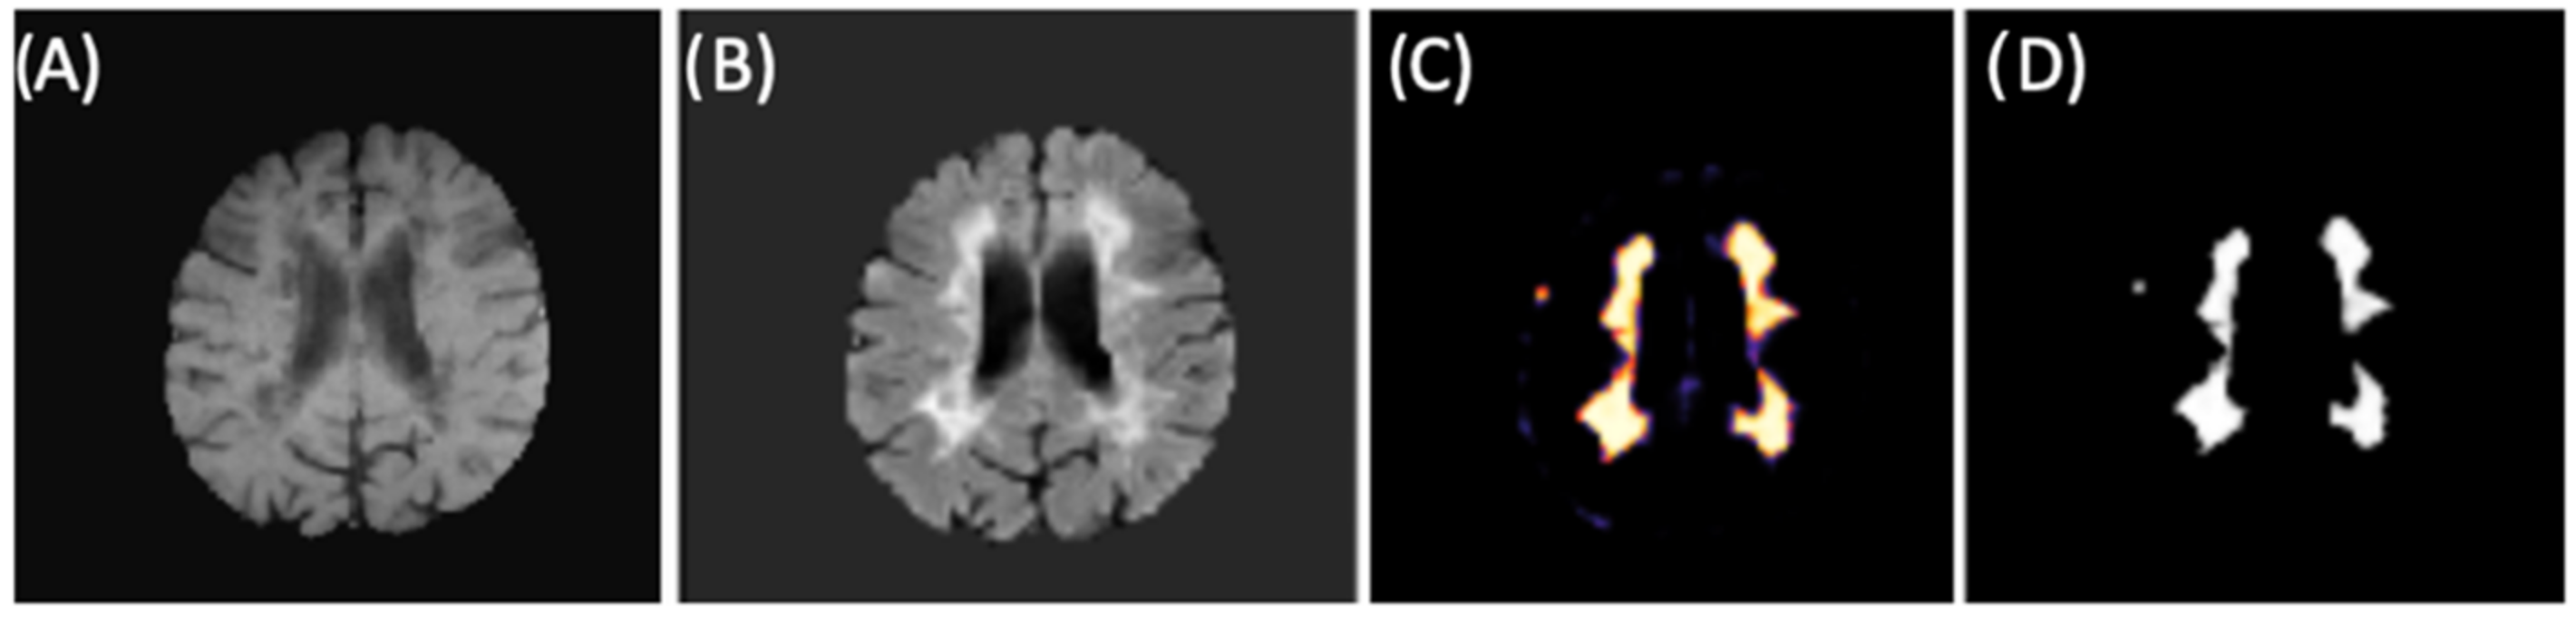

The final training model obtained from the second CNN (as described in Materials and Methods 2.3 and in Figure 2) was used for brain lesion detection, where convolutional blocks were applied to the FLAIR input. From binary mask (outputs), we could detect lesions within new individuals (images) from our test group. Figure 9 shows an example of lesion segmentation on a patient from the test group.

Figure 9.

CNN example for lesion segmentation. (A) T1-w image after preprocessing and brain extraction. (B) FLAIR image after preprocessing and brain extraction (second CNN input). (C) Lesion memberships. (D) Binary mask by thresholding the probabilistic memberships.